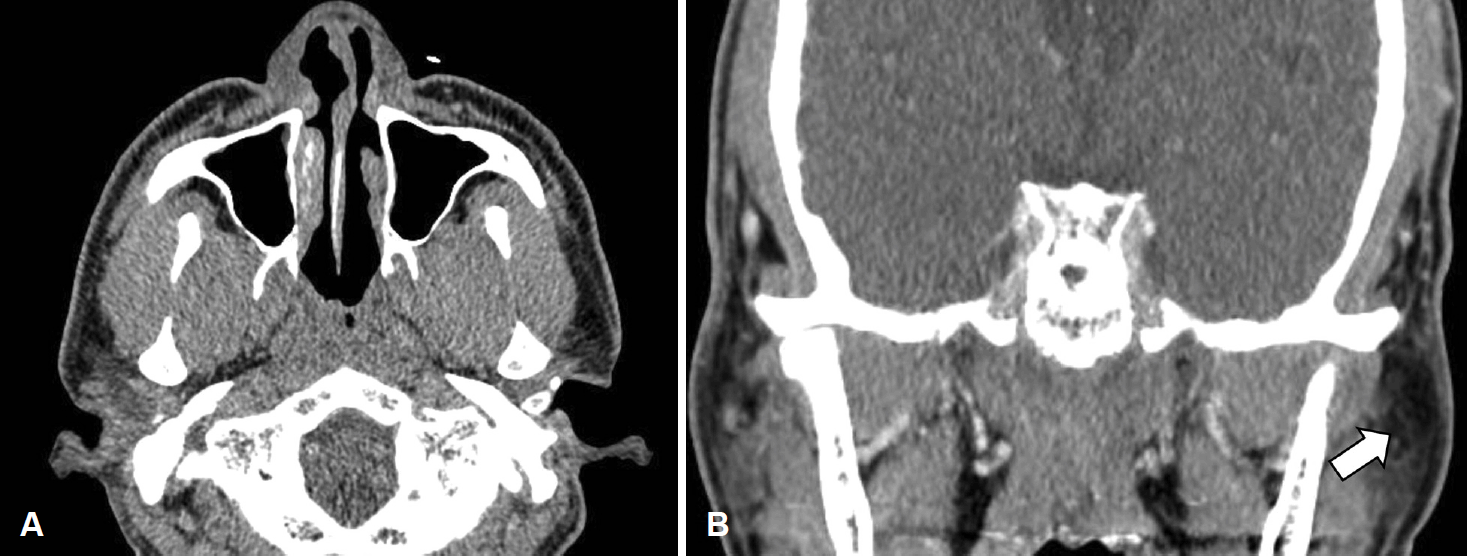

수술 후 1달 째 환자의 경부 종물 크기가 증가하여 경부 전산화단층촬영을 시행하였고, 양측 경부 구역 1b, 2, 3과 좌측 경부 5b, 이하선 내측에서 비괴사성 저음영의 림프절병증이 확인되었다(Fig. 4). 임파선 절제 생검에서도 비인두 종물의 조직소견과 같은 비건락성 육아종으로 사르코이드증에 가까운 소견을 보였으나 수술 후 40일 째에 비인두 조직 배양검사에서 결핵균의 배양이 확인되어 항결핵제 이소니아지드(isoniazid), 에탐부톨(ethambutol), 리팜핀(rifampin), 피라진아미드(pyrazinamide) 복용을 시작하였다. 흉부 단순촬영상에서 폐결핵 소견은 보이지 않았고, 환자가 알고 있는 결핵 병력은 없었으나 QuantiFERON-TB 검사상 양성소견이었다. 이때 흉부 전산화단층촬영을 권유하였으나 환자가 거부하여 수술 후 6개월째에 시행한 결과, 폐 우상엽과 좌하엽에서 경계가 뚜렷하지 않은 불분명하고 비특이적인 미세결절성 침윤이 확인되었다(Fig. 5). 결핵과 사르코이드증이 정확히 감별되지 않았으나 호흡기내과와 협진으로 비인두 조직 배양검사상 결핵균이 확인되었기에 결핵에 의한 병변으로 판단하여 치료하는 것이 적절하다고 생각하였다.

Neck CT findings 1 month after the operation. Axial (A) and coronal (B) image of neck CT showed multiple non-necrotic hypoattenuated lymphadenopathy in left intraparotid (arrow), both level 1b, 2 (arrowhead: left level 2), 3, and left level 5b.